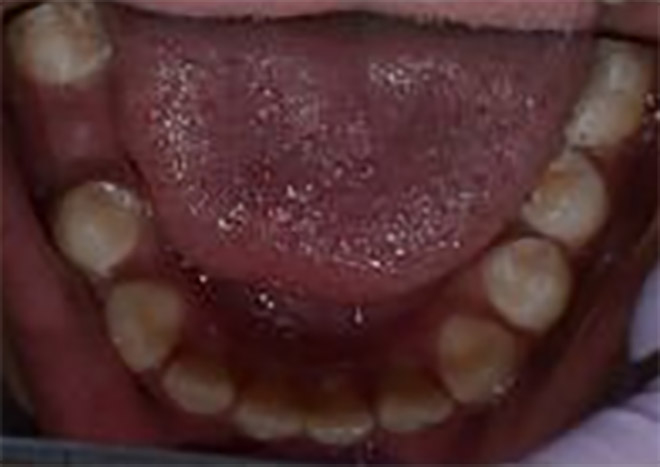

Pre Tx Diagnostic Models

Figures 7 & 8 diagnostic models from first visit